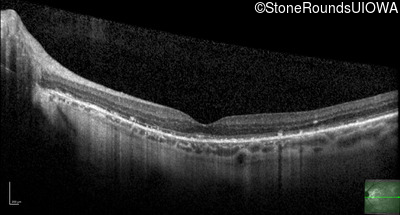

Optical Coherence Tomography - Left - 20/20 -2

Exemplar / OCT Stack

OCT Stack